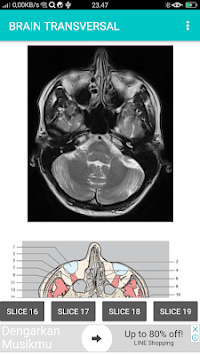

SECTIONAL ANATOMY MRI

POCKET ATLAS MRI is developed by Multirez and is available for free on the Google Play Store. POCKET ATLAS MRI has 5000 installations so far, with a required Android version of 4.0 and up. SECTIONAL ANATOMY MRI

Screenshots